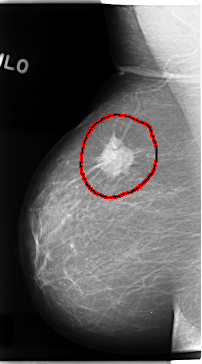

C_0121_1.RIGHT_MLO

FILE: C_0121_1.RIGHT_MLO.OVERLAY

TOTAL_ABNORMALITIES 1

ABNORMALITY 1

LESION_TYPE MASS SHAPE IRREGULAR MARGINS SPICULATED

ASSESSMENT 5

SUBTLETY 5

PATHOLOGY MALIGNANT

TOTAL_OUTLINES 1

BOUNDARY